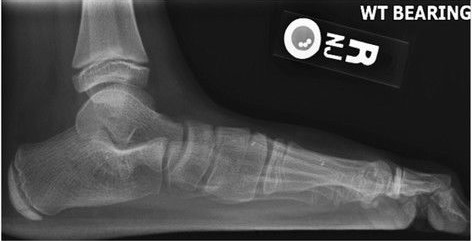

扁平足出现足痛和小腿痛可以到医院检查。过去医生常让患者双脚底沾水后踩在纸上,看足底印迹,如果脚心没有水印,只有前足、足外侧和足跟有印迹就是正常。如果整个足底铺满水印就是扁平足。还可以拍摄站立位的足部X光片、CT或核磁来具体分析足的形态。